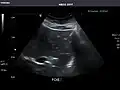

Renal ultrasonography

Ultrasonography of the kidneys is essential in the diagnosis and management of kidney-related diseases. The kidneys are easily examined, and most pathological changes in the kidneys are distinguishable with ultrasound.[7]

Kidneys: Right and left kidneys measure 11.5 cm and 12 cm in length respectively. No hydronephrosis. Small left lower pole kidney cyst.